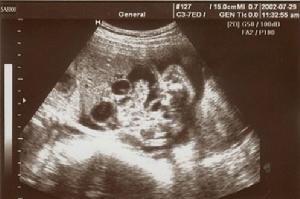

2.B超檢查 除可以作臨床診斷外,還可以用於產前檢查,特別是線陣型實時超聲掃描檢查可顯示十二指腸閉鎖胎兒腹內兩個典型的液區,提示本病的診斷,供出生後正確診斷和有準備地進行治療的參考。